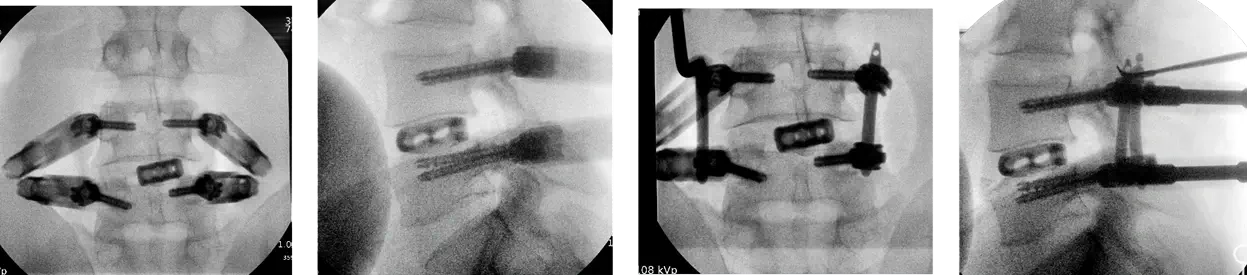

Intra OP

Intra OP radiograhs for the planning of the surgical access.

Placement of the Neo Cage

After the placement of the Neo cage, another 2 Neo pedicle screwswere inserted at the left side,

• L4: Ø6.0x45 mm

• L5: Ø6.0x45 mm

2 X titanium rods, straight 40mm/45mm, were placed.